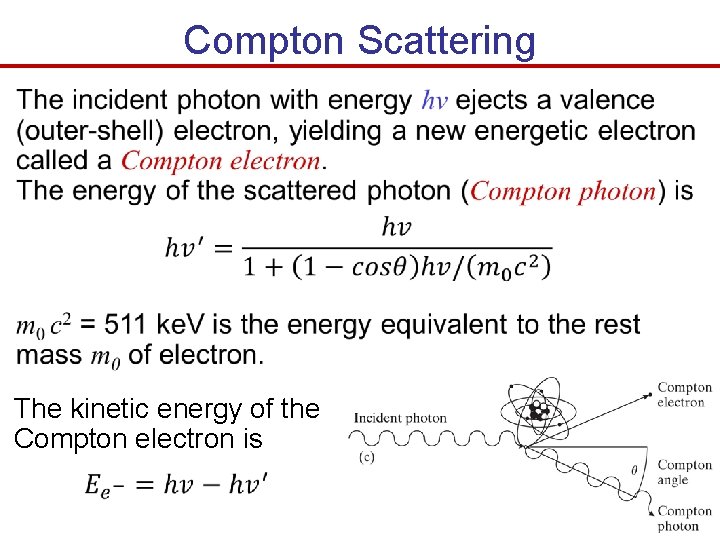

Primary Electromagnetic Radiation Interactions The three main mechanisms by which EM ionizing radiation interacts with materials to from images are: 1. The photoelectric effect - Incident x-ray photon totally loss energy to the atom’s electron cloud. - Provide contrast between different types of tissues in the medical image. 2. Compton scatter - Incident x-ray photon partially loss energy to the atom’s electron cloud and change direction. - Limit the resolution of x-ray images. 3. Pair production (need high energy 1. 02 Me. V so it isn’t applicable in medical imaging 25 - 500 ke. V).

Primary Electromagnetic Radiation Interactions photoelectric effect Compton scattering Figure 4. 6 The photoelectric effect, shown in (a) and (b), and Compton scattering, shown in (c).

Compton Scattering The kinetic energy of the Compton electron is